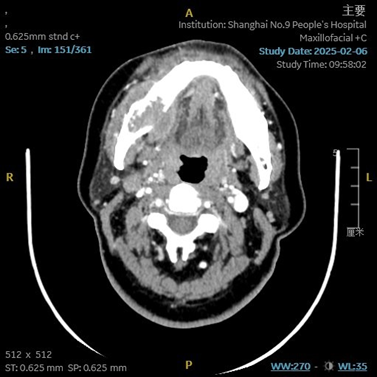

2月13日清晨8点半,张志愿院士再次认真细致阅读当日首台手术患者的影像学资料,确定手术方案,并制定是否即可行功能重建的预案。这位因颌骨中心性癌累及口底的患者,曾在多地求医未果。面对肿瘤侵犯范围广、重要神经血管密布的手术危险区。张志愿院士以规范化、标准化、人性化的一个术者必备的基本素质聚精会神,一丝不苟,边讲边仔细解剖、分离保护重要神经血管,根据术中发现髁突与影响学一致,即按原设计方案行修复术。据统计,春节后1周内院士带领博士团队已完成4例中晚期口腔癌联合根治术及同期显微外科修复术,护理团队负责人表示:“每台手术都超过8小时,2月13日这天同时完成2例复杂口腔癌的根治及修复手术。”至今日发稿张院士又开了两例手术,其中一例是患有多种系统性疾病的高风险病人。

例1右侧下颌骨中心性鳞癌T4N1bM0

保留髁突右半侧下颌骨口底病灶扩大切除术及功能性颈淋巴清扫术,带血管的腓骨肌皮瓣行下颌骨口底缺损修复术。